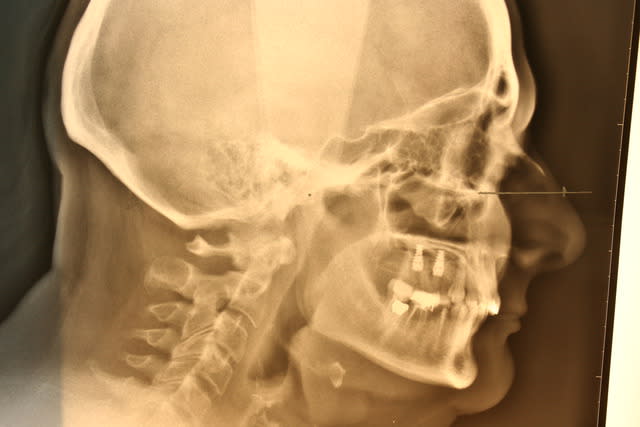

j'ai zappé le début du traitement. Elle s'est présenté avec avulsion récentes de 26 et 27 dans des conditions bizarres, genre elle avait des douleurs dans la zone, un stomato à viré les dents et ça n'a rien changé ..

elle a eu gouttière en relation centrée un moment, puis avec l'amélioration des symptomes, (j'ai juste amélioré son calage je pense) on est passé au fixe, avec augmentation de la DV. Il y a eu implants 25 26 après sinus lift, couronne 36, bridge 45/47, onlay 16 et facettes palatines en composite de 13 à 23 et composites sur les incisives en bas

depuis ça va mieux, je suis juste déçu par l'articulé inversé de la 27 mais la position de l'implant ne permettait pas vraiment autre chose (encore qu'en jouant sur la couronne 36 et en vestibulant un peu les couronnes sur implant ça aurait peut être pu passer)

4 t l radio ape4aa - Eugenol